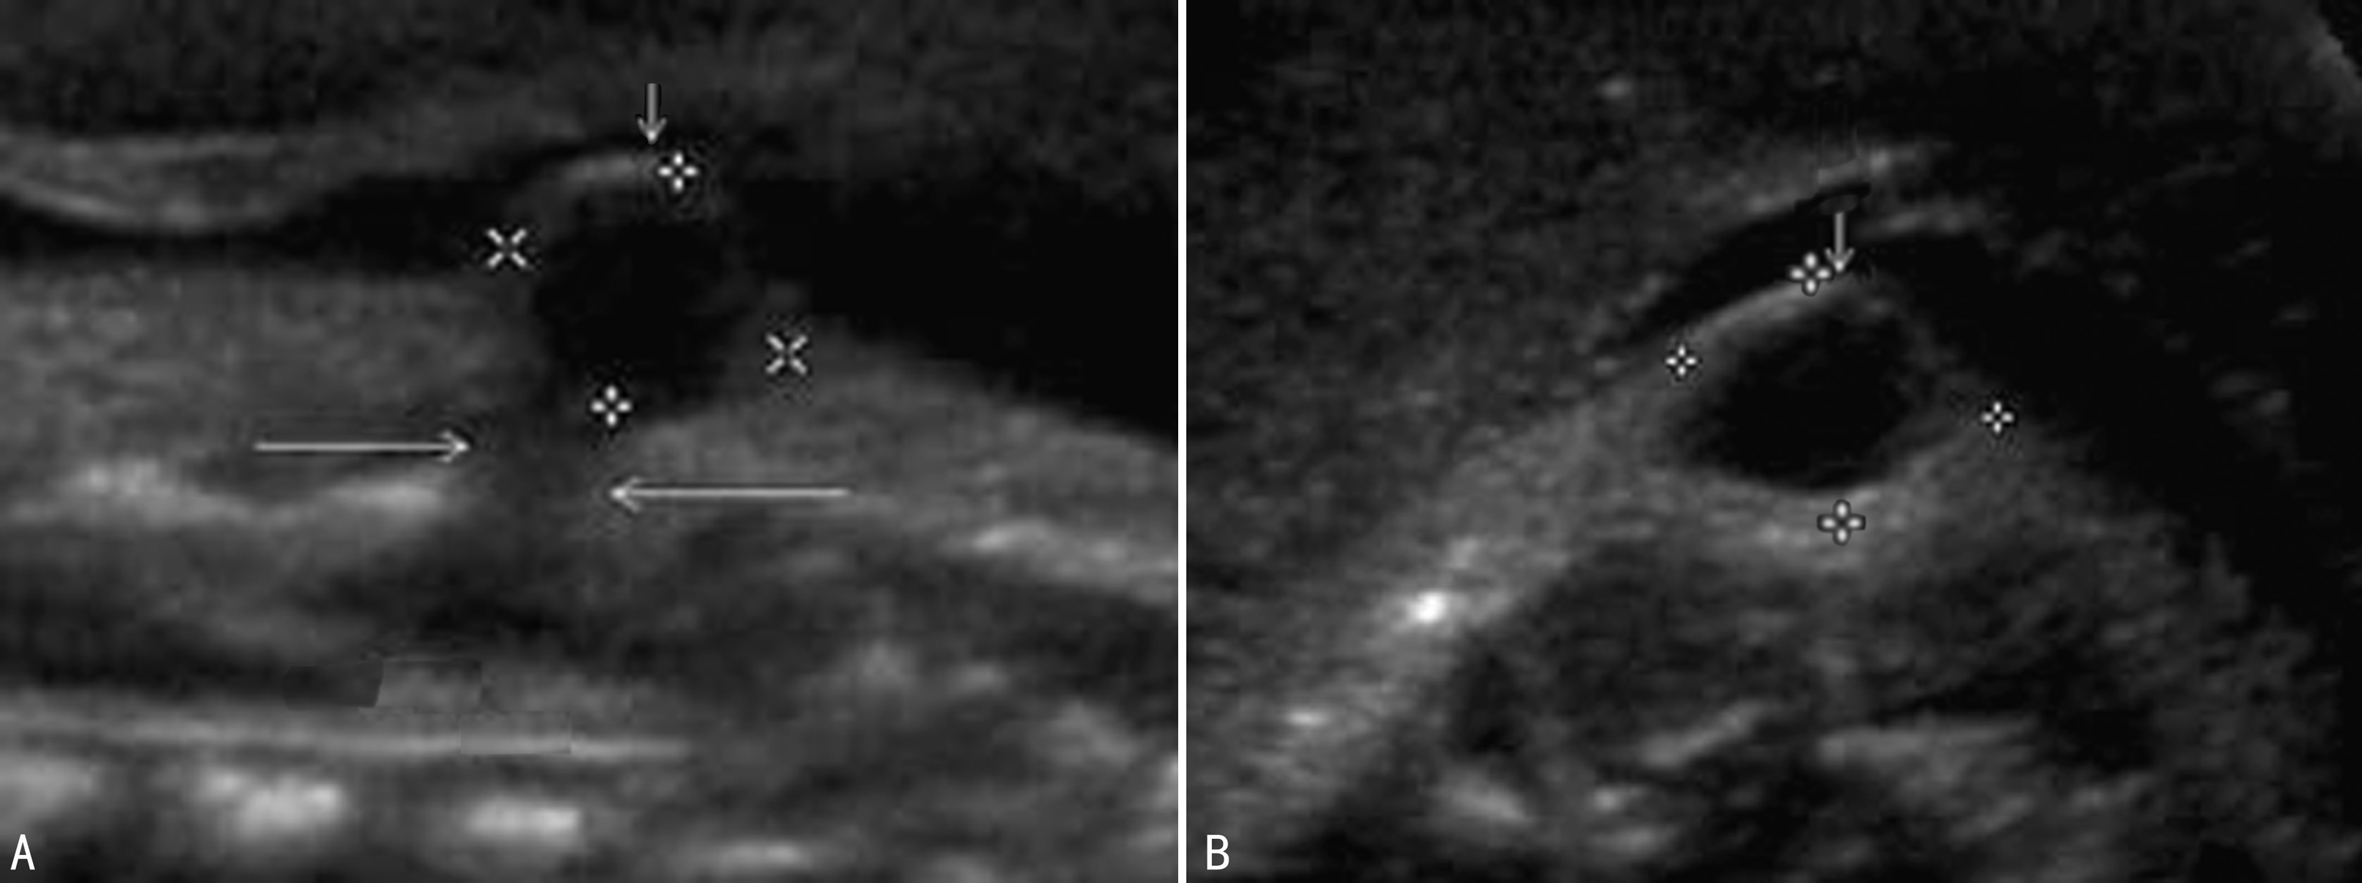

CSD类型不同,声像图表现各不相同。包块型CSD除局部皮肤完整外脊柱的声像图特征与OSD相同,横切面脊椎三角形骨化中心显示不清(图4、图1)或失去正常形态,位于后方的两个椎弓骨化中心向两侧分开,呈“U”形或者“V”形改变。脊柱冠状切面显示后方的两条平行的椎弓骨化中心在裂开处异常增宽,距离增大或部分消失。矢状面上突出的包块内可以看到由脑脊液形成的无回声,或由脊膜脊髓膨出的脑脊液内的不规则低回声组织(图5)。无包块型CSD的脊柱声像改变不明显,产前超声诊断困难。

图4 CSD脊膜膨出矢状面(A)及横断面(B)声像图(箭头)